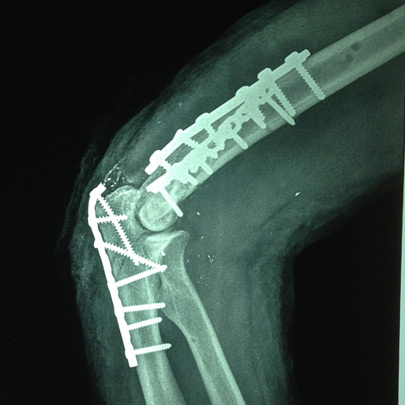

Fracturas y luxaciones

Cirugía de codo